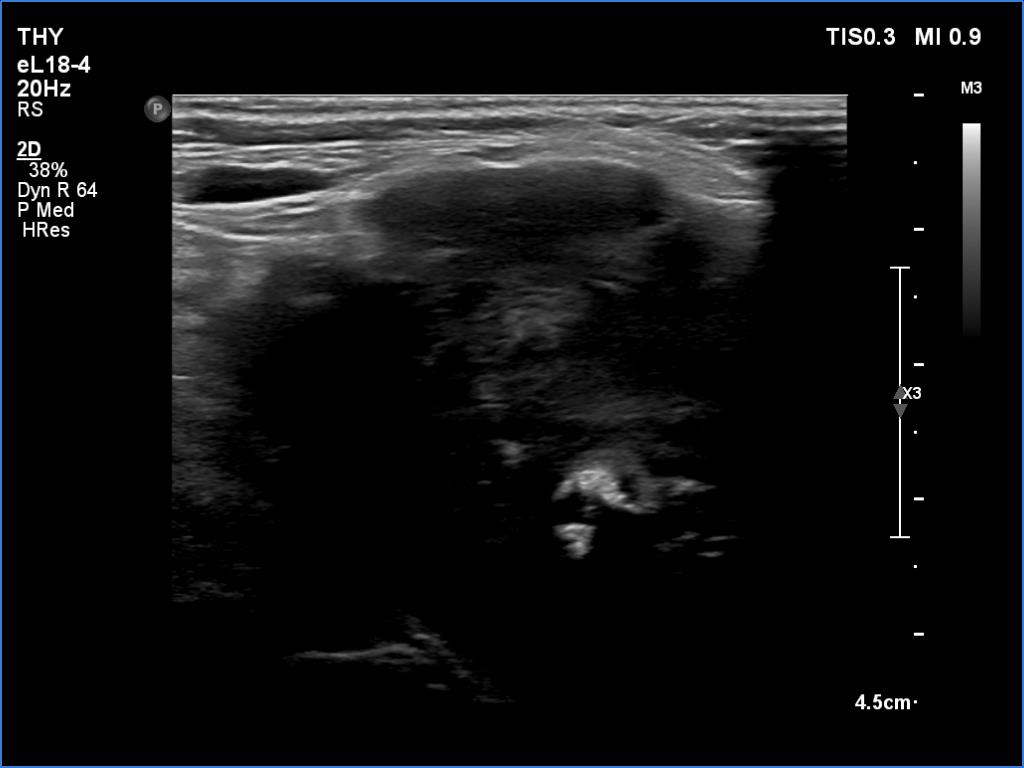

Thyroid cancers - case 1174 (ultrasonographic picture 7)

Right lobe, another longitudinal view - with more harmonization.